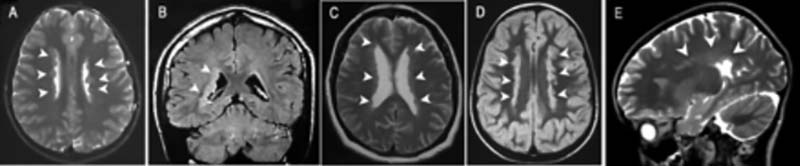

图1.携带FLNA变异的女性患者的脑部成像文献报道的患者脑部存在广泛的连续性或非连续性的脑室周围结节状异位组织病变,病变涉及侧脑室的主体区和三角区[2]